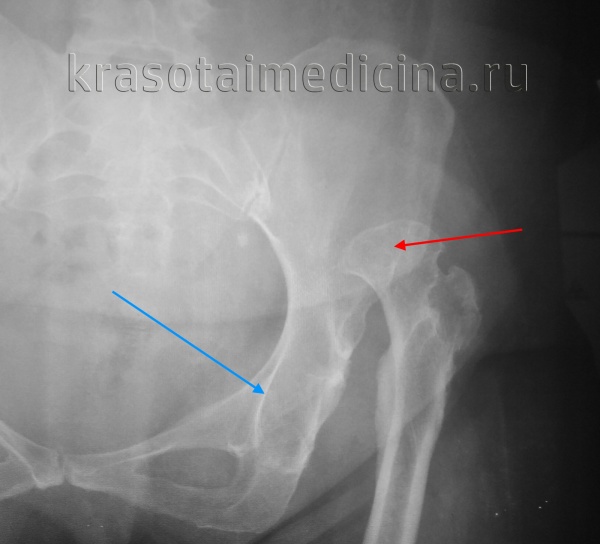

Rg правого тазобедренного сустава. Врожденный вывих бедра. Головка бедренной кости (красная стрелка) ремоделирована, уплощена, смещена краниально. Вертлужная впадина (синяя стрелка) недоразвита.

КТ таза. 3D-реконструкция. Красная стрелка – вывихнутая головка бедренной кости, синяя стрелка – «пустая» вертлужная впадина.